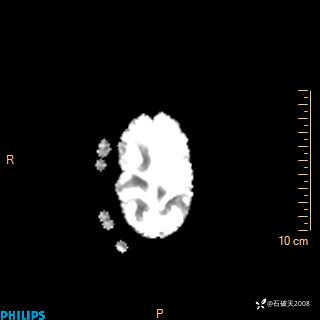

2020.11.14MR

DWI

ADC